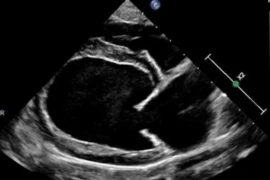

Dr. Michael Aherne is a Clinical Assistant Professor of Cardiology at the University of Florida College of Veterinary Medicine. He is originally from Ireland where he graduated with a first-class honors degree in Veterinary Medicine from University College Dublin. After graduating, he subsequently spent several years in small animal general practice in Queensland, Australia before completing his rotating internship at the University of Sydney in Australia where he also completed a Graduate Diploma in Veterinary Clinical Studies and was also successfully admitted by examination as a Member of the Australian and New Zealand College of Veterinary Scientists in 2012. Following a brief return to private practice in Sydney, he then moved to the USA to complete his cardiology residency as well as a Master’s degree in Biomedical and Veterinary Science at the Virginia-Maryland College of Veterinary Medicine, Virginia Tech and became a Diplomate of the American College of Veterinary Internal Medicine (Cardiology) in 2017, following which, he took up his current position at the University of Florida. His areas of interest include cardiac surgery, interventional cardiology, congenital cardiac disease, electrophysiology, advanced cardiac imaging techniques and veterinary education.